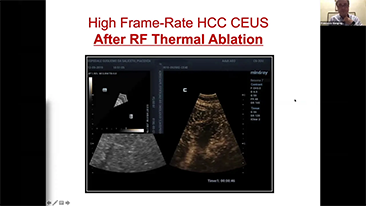

Para las lesiones hepĂĄticas focales, como el hemangioma o el cĂĄncer de hĂgado, el diagnĂłstico por imĂĄgenes mediante ecografĂa con contraste cumple un papel importante. La tecnologĂa de diagnĂłstico por imĂĄgenes con contraste UWN+ (no lineal ultraancha) puede ayudar a obtener una mejor penetraciĂłn, una mayor relaciĂłn contraste-tejido, con un IM mĂĄs bajo y una observaciĂłn del tiempo de perfusiĂłn mĂĄs prolongada.